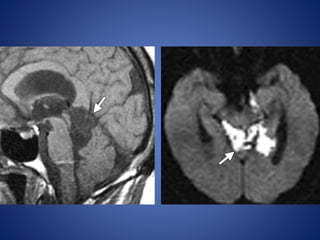

• #63 Drawing illustrates cranial nerve IV nuclei in the midbrain at the level of the inferior colliculus (IC). CA = cerebral aqueduct, CST = corticospinal tract, IV = cranial nerve IV, SN = substantia nigra, ST = spinothalamic tract, TN = trochlear nerve nucleus Epidermoid tumor in a 63-year-old man who presented with intermittent diplopia and seizures axial T2-weighted (c) MR images show a mass that is isointense relative to cerebrospinal fluid (arrow) compressing the left trochlear nerve in the ambient cistern.

• #64 Sagittal T1-weighted and axial diffusion-weighted MR image, the mass restricts diffusion (arrow), a finding that strongly supports the diagnosis of epidermoid tumor.